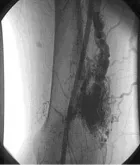

Background: Congenital Vascular malformation relatively rare and extremely varied clinical presentations. The purpose of our study was to present our initial experience of embolization in a series of 26 patients with congenital vascular malformation to assess retrospectively the results and the complications of ethanol and coils embolization treatment of these patients.

Methods: Retrospective trial, the study group consisted of 26 patients with congenital vascular malformations. Transcatheter arterial embolization by ethanol or coils were performed, Therapeutic outcomes were established by evaluating the clinical outcome of symptoms and signs, as well as the degree of devascularization at follow-up angiography.

Results: Between November 2014 and March 2018, 26 consecutive patients (3 male, 23 female) at Alshifa Hospital - Cardiac Catheterization Center with congenital vascular malformations in the body and extremities underwent staged ethanol or coils embolization. The mean age of the patients was 25 years (age range, 6– 59 years). Ethanol embolization was administrated in 16 patients, coil embolization in 9 patients and graft stent in one patient. The side effect such as pain, pulsation, and bruit in most of the patients were obtained. The reduction of redness, swelling, and warmth was achieved in all of the patients, According to the angiographic findings, congenital vascular malformation were devascularized 100% in 12 patients, 50% to 99% in 11 patients, less than 50% in 3 patients. The most common complications were reversible skin necrosis.

Conclusion: Transcatheter embolization by ethanol or coils has proved efficacious and safe in the treatment of congenital vascular malformation of the body and extremities but with acceptable risk of complications